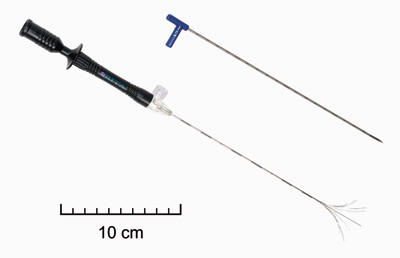

To ulike systemer for radiofrekvensablasjon ble brukt i perioden. Et system med perfusjonselektroder (Elektrotom HiTT 106, Berchtold GmbH & Co, Tuttlingen, Tyskland) ble benyttet til de første 11 pasientene. Fra 2005 benyttet vi et system med paraplyelektroder (RITA model 1500, RITA Medical Systems, Mountain View, CA) (fig 1). Kontrastforsterket ultralyd (n = 12), intraoperativ ultralyd uten kontrast (n = 4) eller MR (n = 1) ble brukt for å plassere elektroden og monitorere utbredelsen av vevsødeleggelsen. Optimal elektrodeposisjon ble bestemt ut fra elektrodens karakteristika samt tumors geometri og beliggenhet i forhold til intrahepatiske kar. Ablasjon ble gjennomført når elektrodeposisjonen var akseptabel.